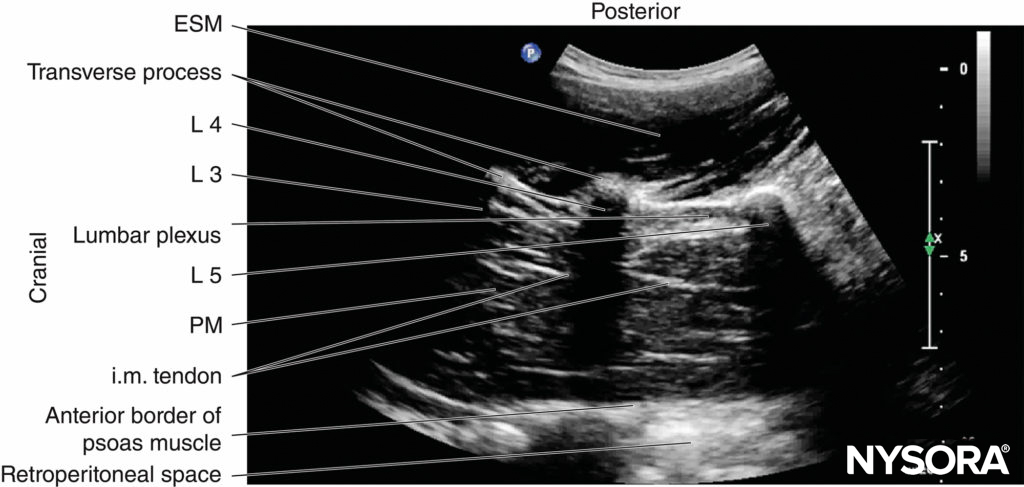

FIGURE 11. Sagittal sonogram of the lumbar paravertebral region showing the lumbar plexus as a hyperechoic structure in the posterior aspect of the psoas muscle (PM) between the L4 and L5 transverse processes. Also note the hyperechoic intramuscular tendons within the bulk of the psoas muscle. ESM, erector spinae muscle; i.m. tendon = intramuscular tendon.

FIGURE 12. Sagittal sonogram of the lumbar paravertebral region showing the acoustic shadows of the lumbar transverse processes (L3, L4, and L5), which produce a sonographic pattern called the “trident sign.” The psoas muscle is seen in the intervening acoustic window.

On a sagittal sonogram, the lumbar transverse processes are identified by their hyperechoic reflection and an anterior acoustic shadow (see Figures 11 and 12), which is typical of bone. The acoustic shadow of the transverse processes produces a sonographic pattern referred to as the “trident sign” (see Figures 11 and 12) because of its similarity in shape to a trident (in Latin, tridens or tridentis).

The psoas muscle is visualized through the acoustic window (see Figures 11 and 12) of the trident as multiple longitudinal hyperechoic striations against a hypoechoic background typical of muscle (see Figure 11). The lumbar plexus nerves are seen as longitudinal hyperechoic structures in the posterior aspect of the psoas muscle (see Figure 11) One should note that not all hyperechoic shadows or striations within the psoas muscle are nerves because the psoas muscle contains intramuscular tendons, which also produce hyperechoic shadows (Figure 20).

Nevertheless, the nerves of the lumbar plexus can be differentiated from the intramuscular tendons as they are thicker than the muscle fibers, take an oblique course through the psoas muscle (see Figure 11), and are better visualized after local anesthetic injection. A laterally positioned US transducer will produce a “suboptimal” sagittal sonogram without the US “trident,” but with the lower pole of the kidney, which lies anterior to the quadratus lumborum muscle and can reach the L3–L4 level in some patients.